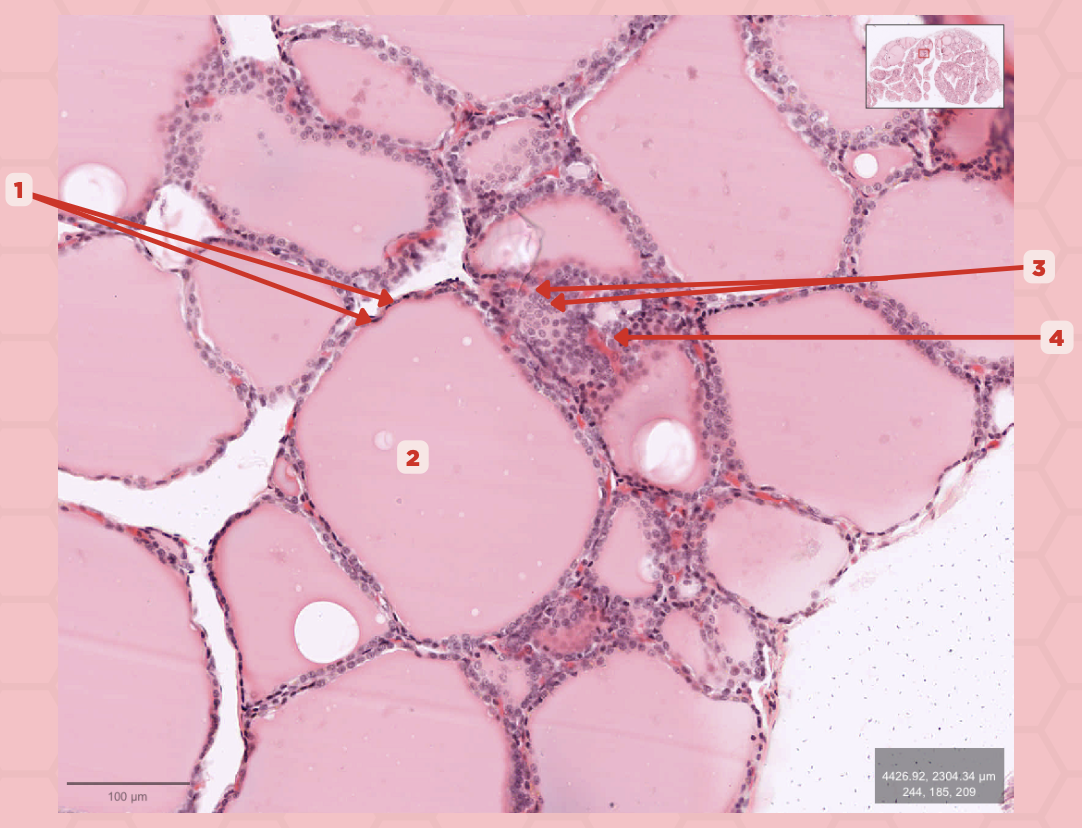

Thyroid

Identify the specimen.

Lobules

Identify the structure labeled as 1.

Follicles

Identify the structure labeled as 2.

T3 and T4 Hormone

What type of hormone is being secreted by the pointer #1?

Follicular Cells

Identify the structure labeled as 1.

Colloid

Identify the structure labeled as 2.

Parafollicular Cells

Identify the structure labeled as 3.

Capillary

Identify the structure labeled as 4.